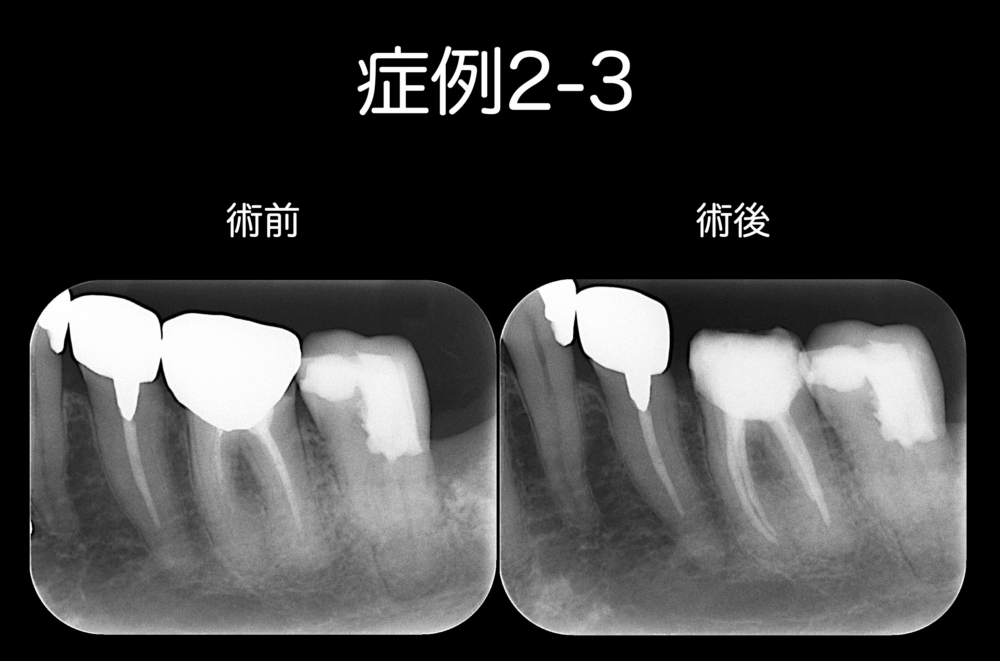

症例2-3は、根管治療前後のレントゲンです。

今後も、経過観察を継続します。